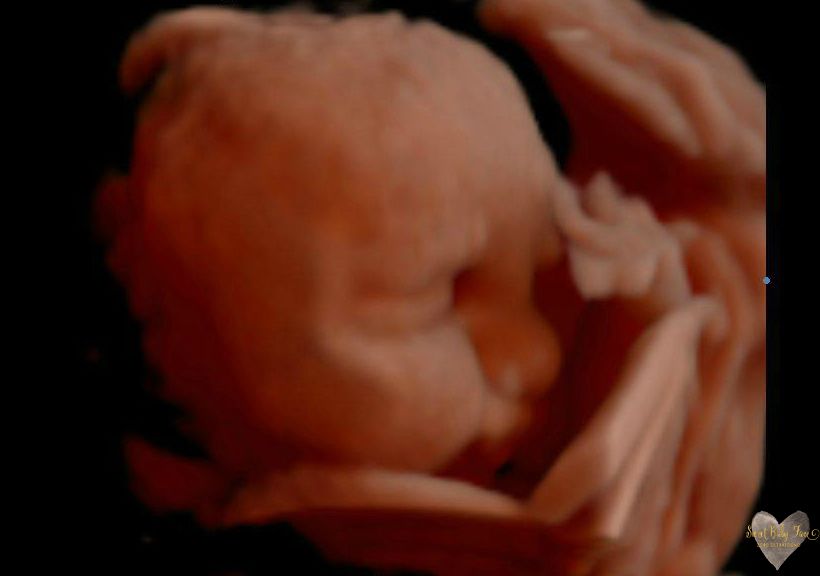

3D/4D/5D Ultrasound Gallery

Take a peek at our Photo Gallery. All of our 2D, 3D, 4D, HD elective ultrasound images are truly ours. They come directly off our machine from our highly trained staff. We can start getting great 3D/4D images as early as 10 weeks!